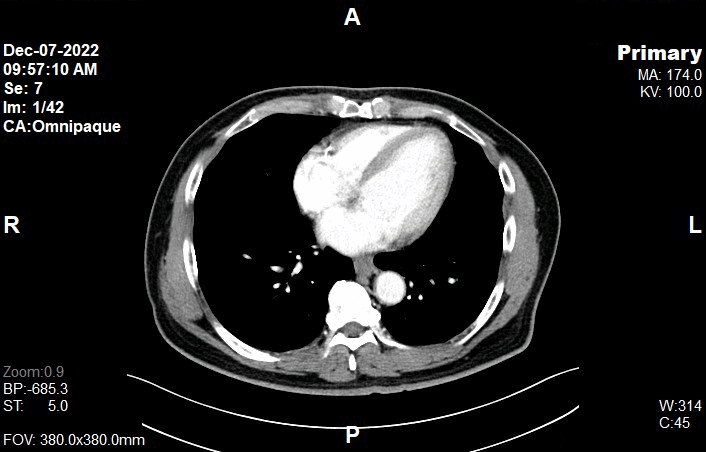

Scanning Parameters

• kV: 100 kV

• mAs: Tube Current Modulation (TCM)

• Scanning Direction: Craniocaudal

• Scan Delay: 4 s

• Slice: 5.0mm

• Image Comment: Pre-Contrast

• Pitch: 0.6

• Quality Reference mAs : 230

Bolus Tracking

Pre Monitoring

• Set the scanning line at the level of diaphragm.

Monitoring

• Ensure the scanning line from Pre-Monitoring is at the level of diaphragm.

• Ensure the lateral line to cover patient’s body outline.

• Draw ‘Triggering ROI’ on Abdominal Aorta (left-hand click on Siemens CT console).

• Set:

• Delay: 10 seconds

• HU to triggered : 100HU